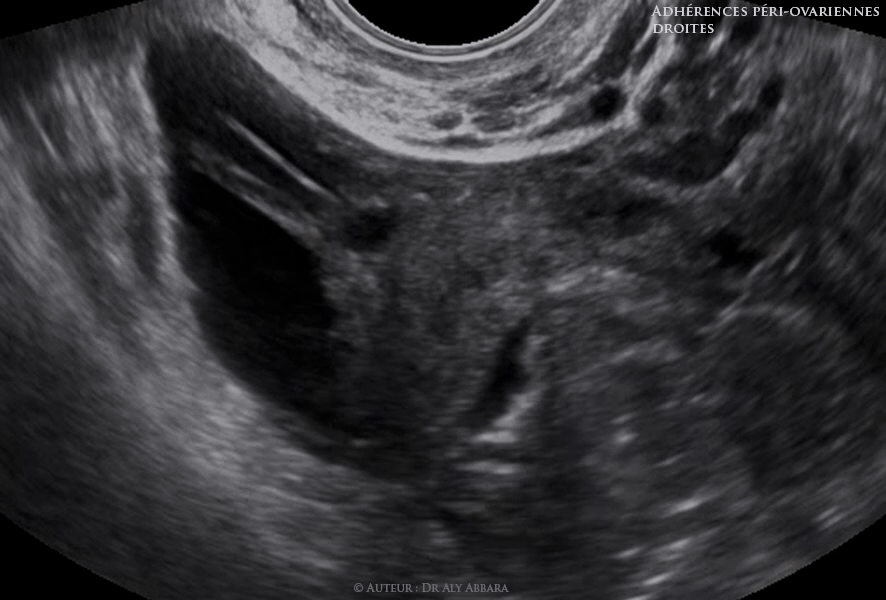

Adhérences péri-ovariennes droites (brides et voiles) fixant l'ovaire à la paroi latérale du pelvis - images échographiques

Séquences vidéo et images échographiques mettant en évidence la présence d'adhérences péri-ovariennes droites sous forme de brides et voiles fixant l'ovaire à la paroi latérale du pelvis.

La présence d'un épanchement péri-annexiel droit a permis de visualiser échographiquement ces phénomènes adhérentiels annexiels droits, ce qui n'est pas le cas au niveau des annexes utérines gauches.

Cliniquement : patiente âgée de 35 ans, mère d'un enfant et consultant pour une infertilité secondaire de 18 mois sans d'autres symptômes ou signes associés.